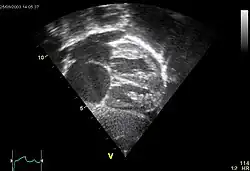

Echokardiogramm eines ASD II, d.h. Ostium-secundum-Typ.

Atrial septal defect (ASD)

ASD II:

Das heruntergewachsene Septum primum reisst normalerweise in der Mitte ein und bildet das Foramen secundum bzw. Foramen ovale. Dieses wird durch das links vom Septum primum ebenfalls von oben herunterwachsende Septum secundum gardinenartig bedeckt (Ventil) und kurz nach der Geburt durch Umkehr der Druckverhältnisse funktionell (z.T. strukturell durch Verklebung) verschlossen. Ist der Verschluss so ungenügend, dass es zum Links-rechts-Shunt kommt, spricht man vom offenen Foramen ovale bzw. ASD II. Der ASD II ist im Ggs. zum ASD I weiter oben lokalisiert. Er macht oft wenig Symptome und wird oft erst im Erwachsenenalter erkannt. Der Links-Rechts-Shunt kann im EKG zu Zeichen der Rechtsherzbelastung führen (Rechtslagetyp, P pulmonale, inkompletter Rechtsschenkelblock ohne Hypertrophie-Zeichen (rsr's') als Zeichen der rechtsventrikulären Volumenbelastung) und bei starker Ausprägung zu klinischen Symptomen führen.